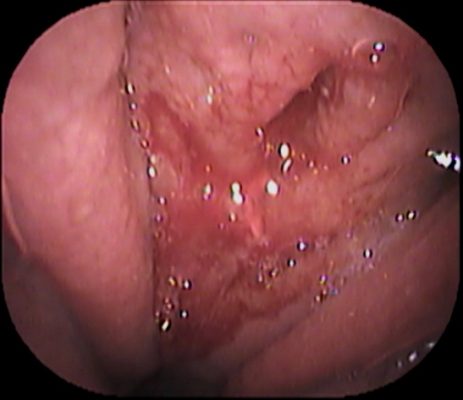

まずは上咽頭をファイバーでチェックしてみます ![]()

![phr-ne11[1]](https://www.inoue-ent-cl.jp/webcms/wp-content/uploads/2022/11/phr-ne111.jpg)

上咽頭に少し 膿が付着していました(赤丸部分)。